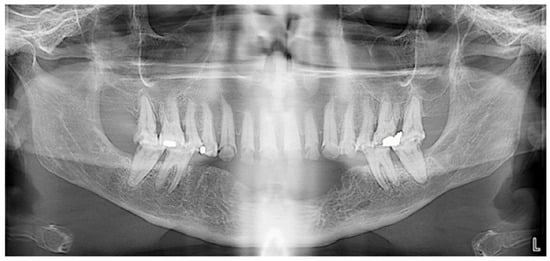

For the mandibular metal-framed removable partial denture, a digital impression was made using the 3Shape intraoral scanner. After the framework try-in, maxillomandibular relationship records were obtained using Aluwax (Aluwax Dental Products Co., Allendale, MI, USA), to accurately mount the casts on the articulator. The set-up was evaluated before polymerization. Upon prosthesis insertion, the occlusion was verified to ensure group function. Figure 1B, Figure 7 and Figure 8 illustrate the final treatment outcome.

Occluded arches views after treatment: (A) right view, (B) front view, (C) left view.

Figure 8.

Panoramic radiograph after treatment.